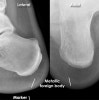

2. Metal foreign body

Dense material such as metal and glass show up easily with X-rays.

Other foreign bodies such as wood may not be dense enough to be visible - in which case use of ultrasound can help determine location.